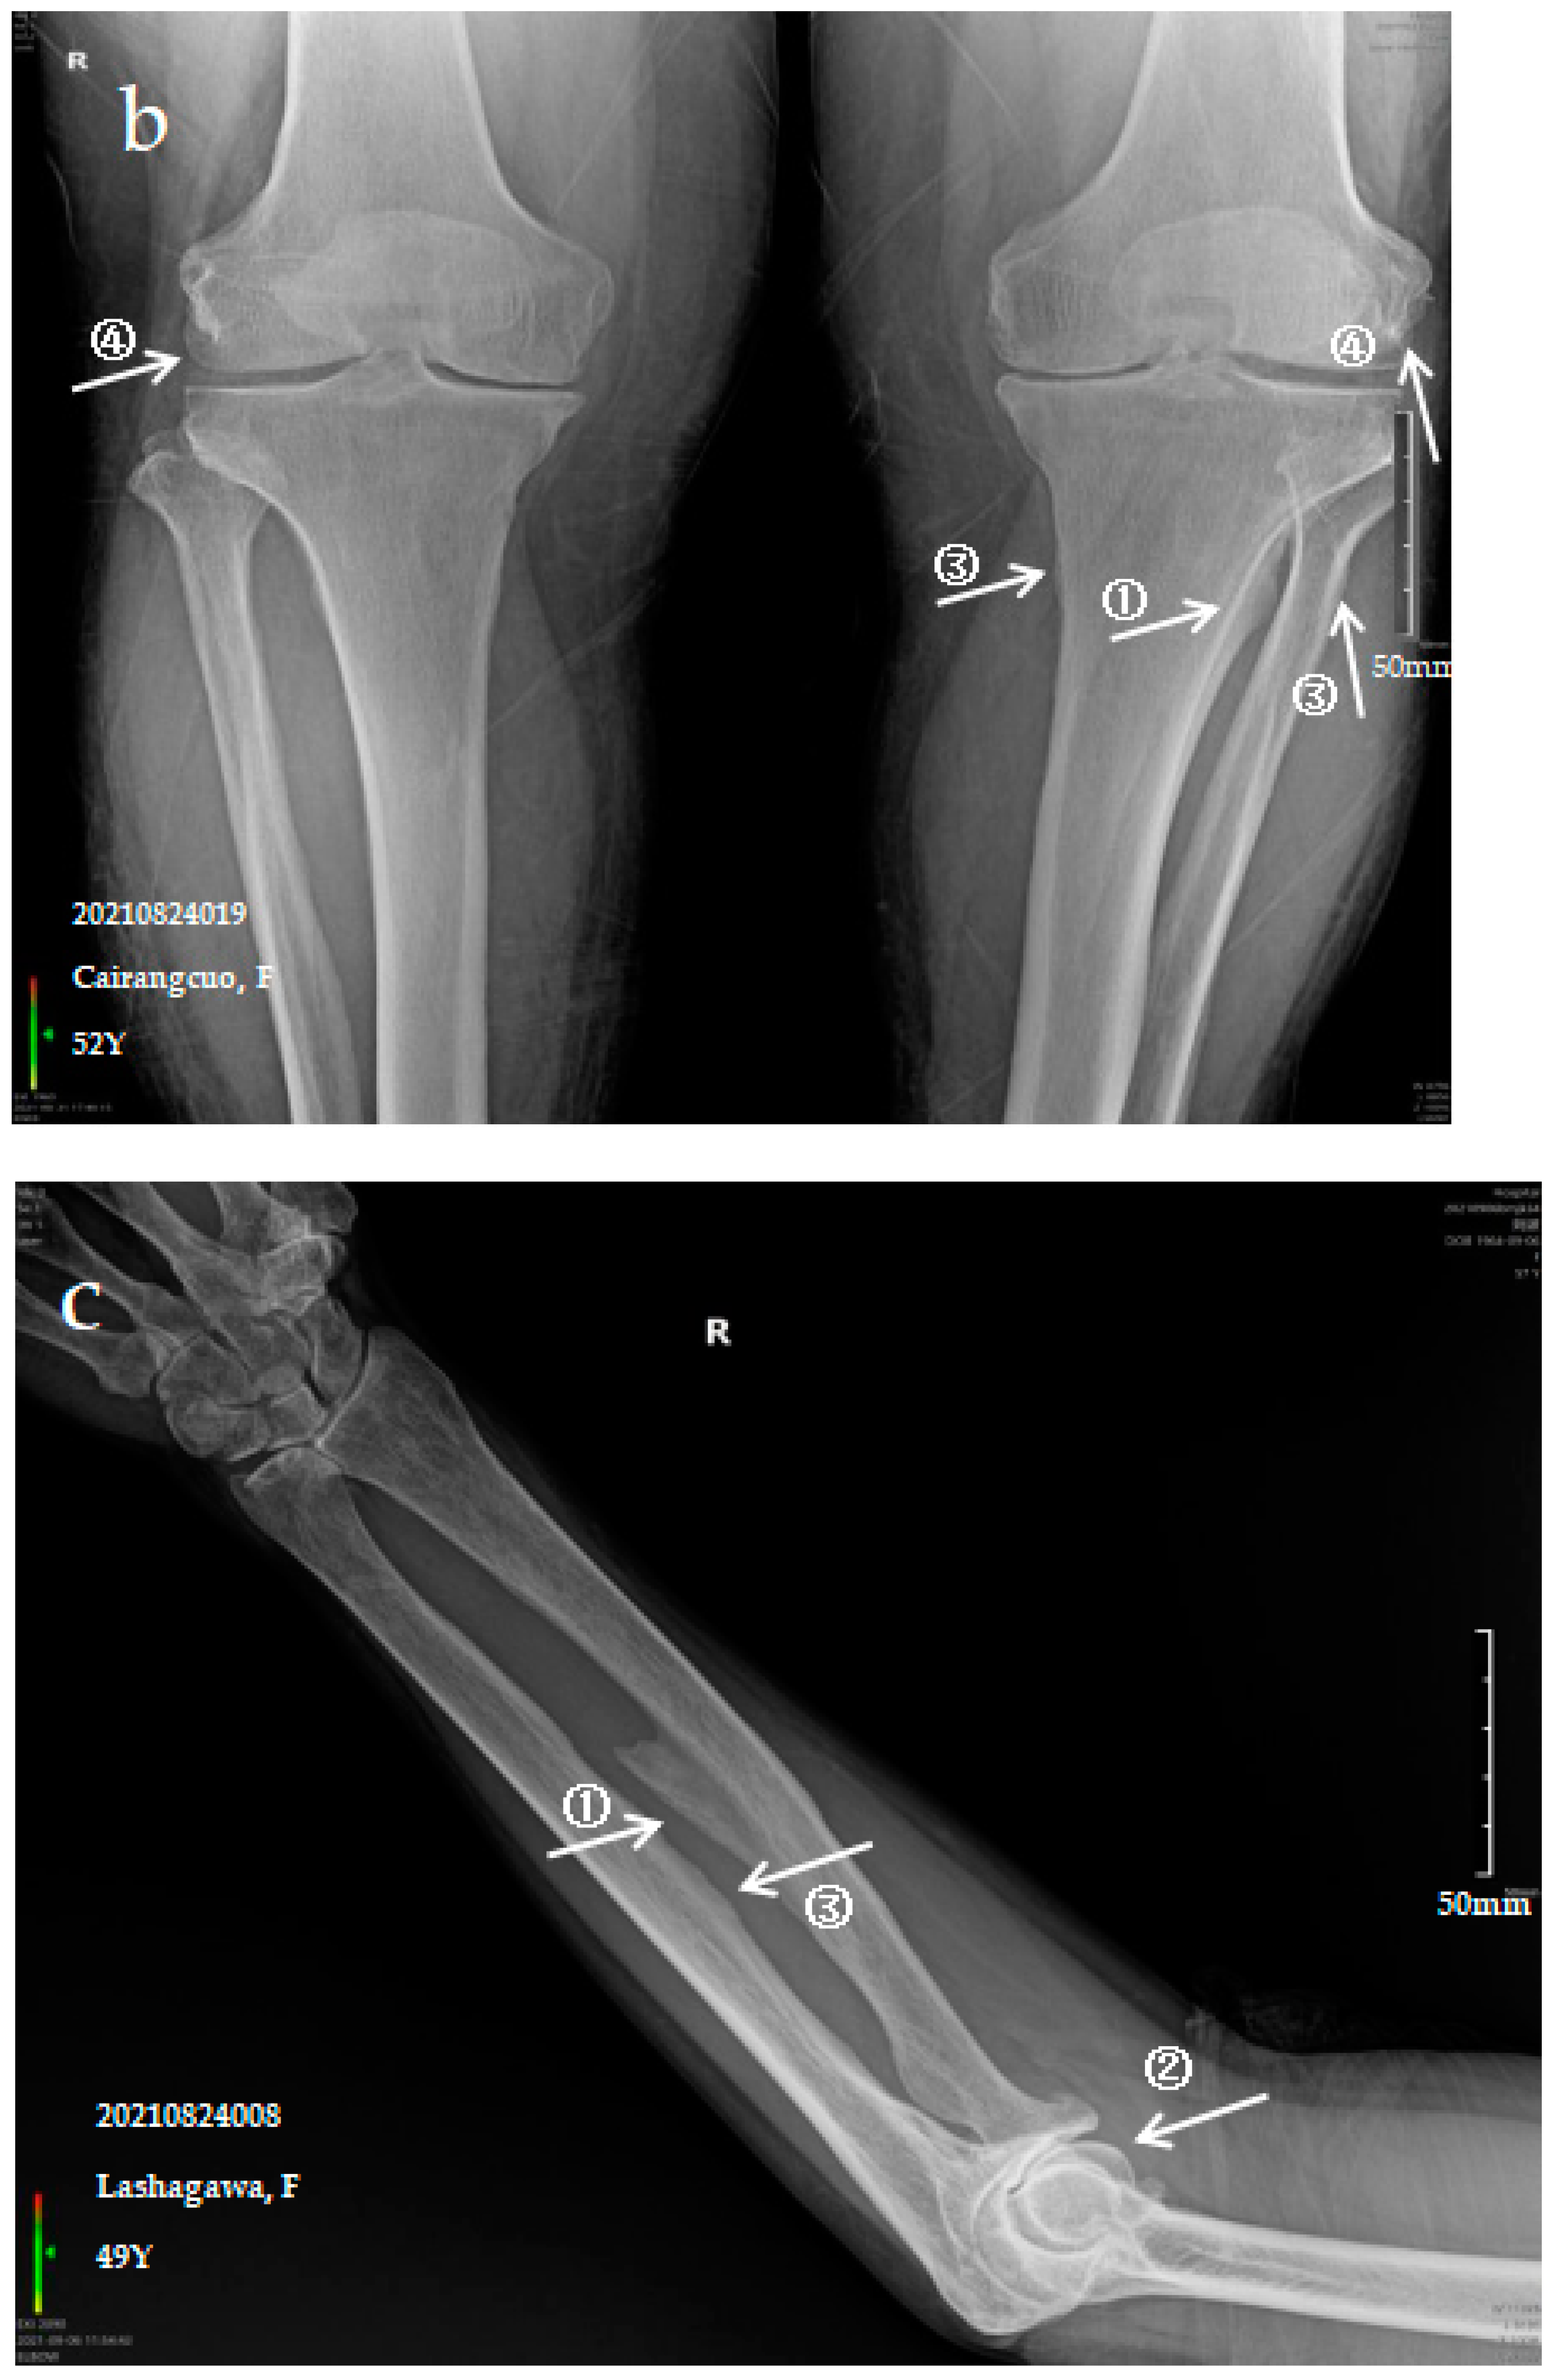

3.2.1. Case Analysis of a Patient Diagnosed by X-ray with Mild SF

3.2.2. Case Analysis of a Patient Diagnosed by X-ray with Moderate SF